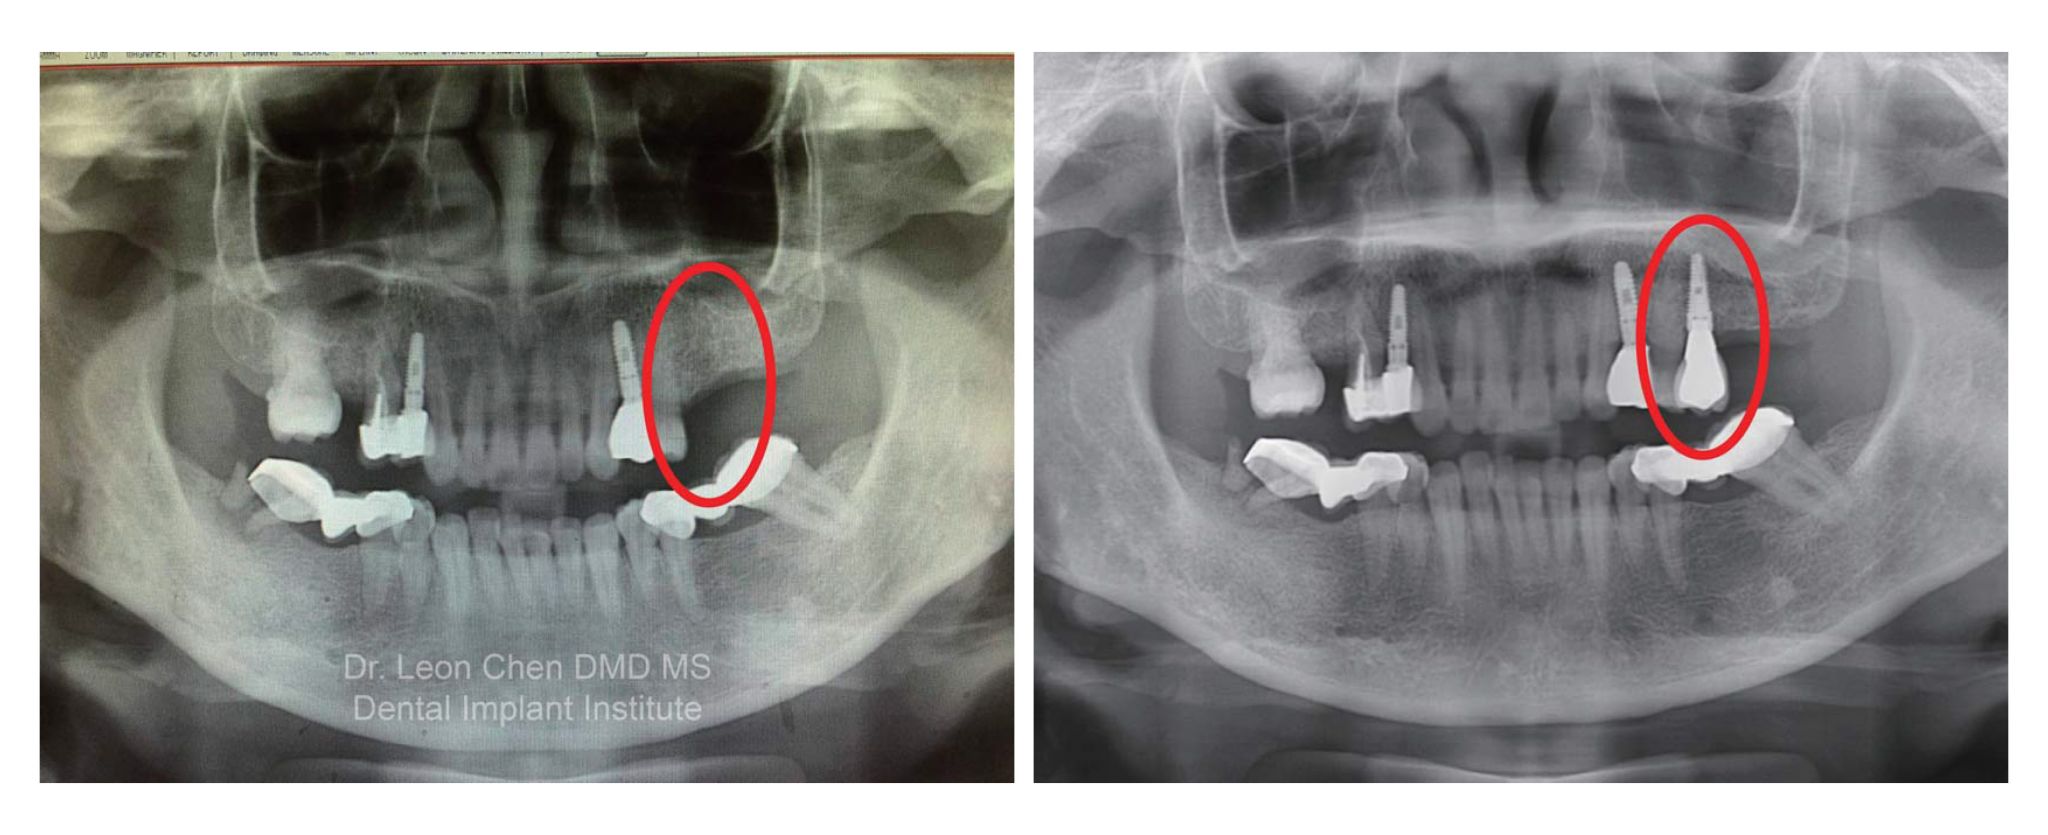

終於到診療那天,細心的陳博士研究我的術前X 光片,向我說明等等要植牙的位置,及所需花費的時間;準備就緒,躺在診療椅上的我,仍有些後悔;貼心的護士捲起一捆一捆的小枕頭,放在我的脖子下方,讓我躺得更舒服些;張開嘴,陳博士一針一針往我的患部周圍打上麻藥,我驚訝地發現:「怎麼不會痛,那地方沒有神經嗎?不對呀!若沒有神經幹嘛打麻藥?還是我昨晚喝太多酒了?也不對呀!原來是真的……他打麻藥一點都不會痛!哇!果真是哈佛名醫。」

從打麻藥到植一顆牙,前後不到2 分鐘完成!

陳博士分析術前術後的X 光片,我傻傻的看著我的X 光片,除了感動還有感謝。我感動的是陳博士幫我克服對植牙的恐懼,在輕鬆的氛圍下完成植牙手術;感謝的是陳博士讓我不再懼怕看牙醫,而且就如陳博士說的,我另一個臉頰有稍微豐腴……植過牙的臉頰完全不出來有浮腫。